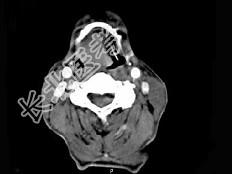

- 单项选择题男,74岁, 咽喉部不适1年余,近两3个月咽喉疼痛, 吞咽困难,CT如图所示, 最可能诊断是 ( )

A、喉癌

B、会厌癌

C、声带癌

D、声门下区癌

E、跨声门型癌